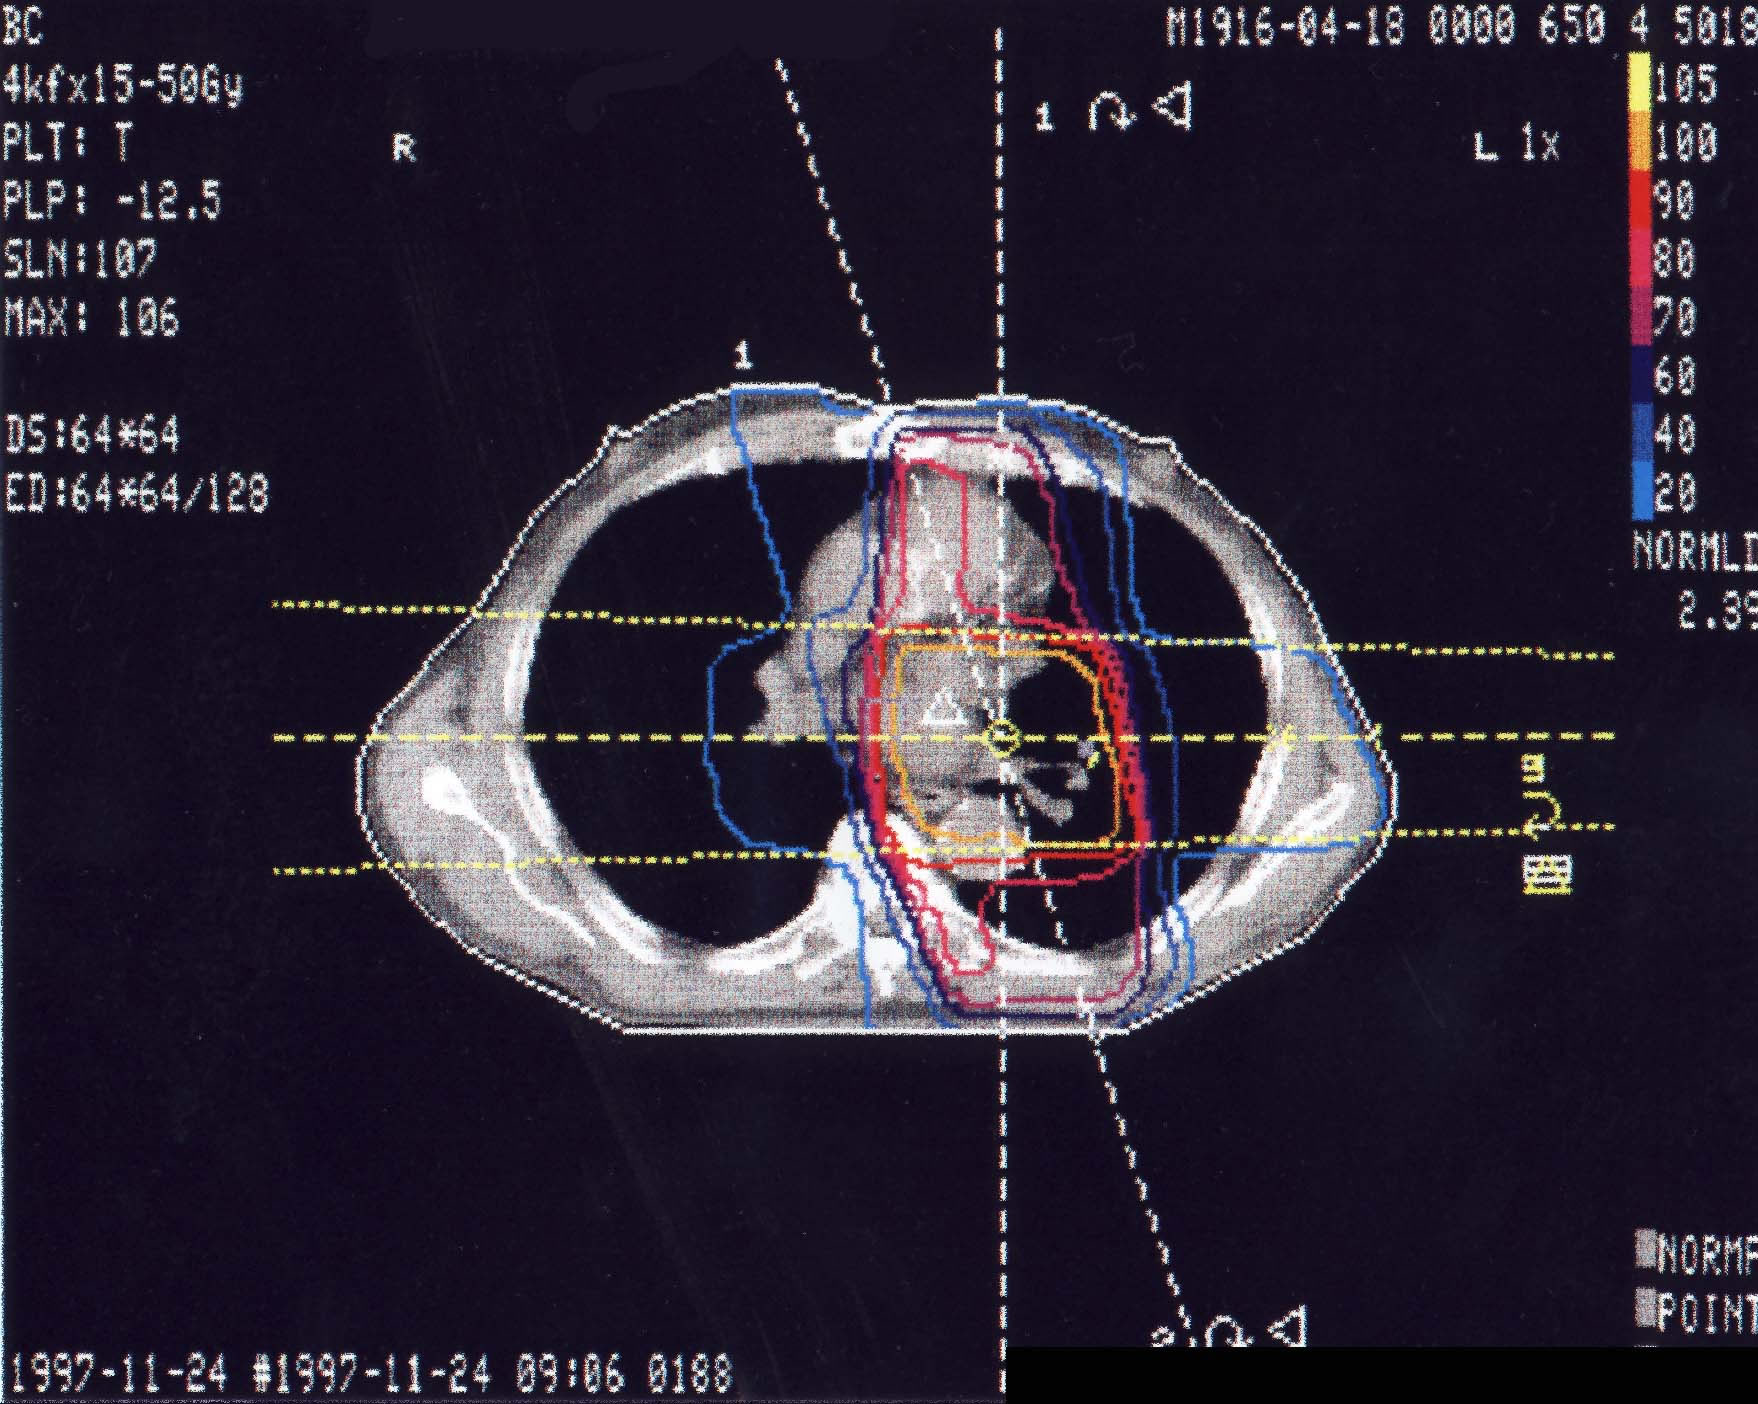

Bronchialkarzinom: Bestrahlungsplan

Bestrahlungspläne